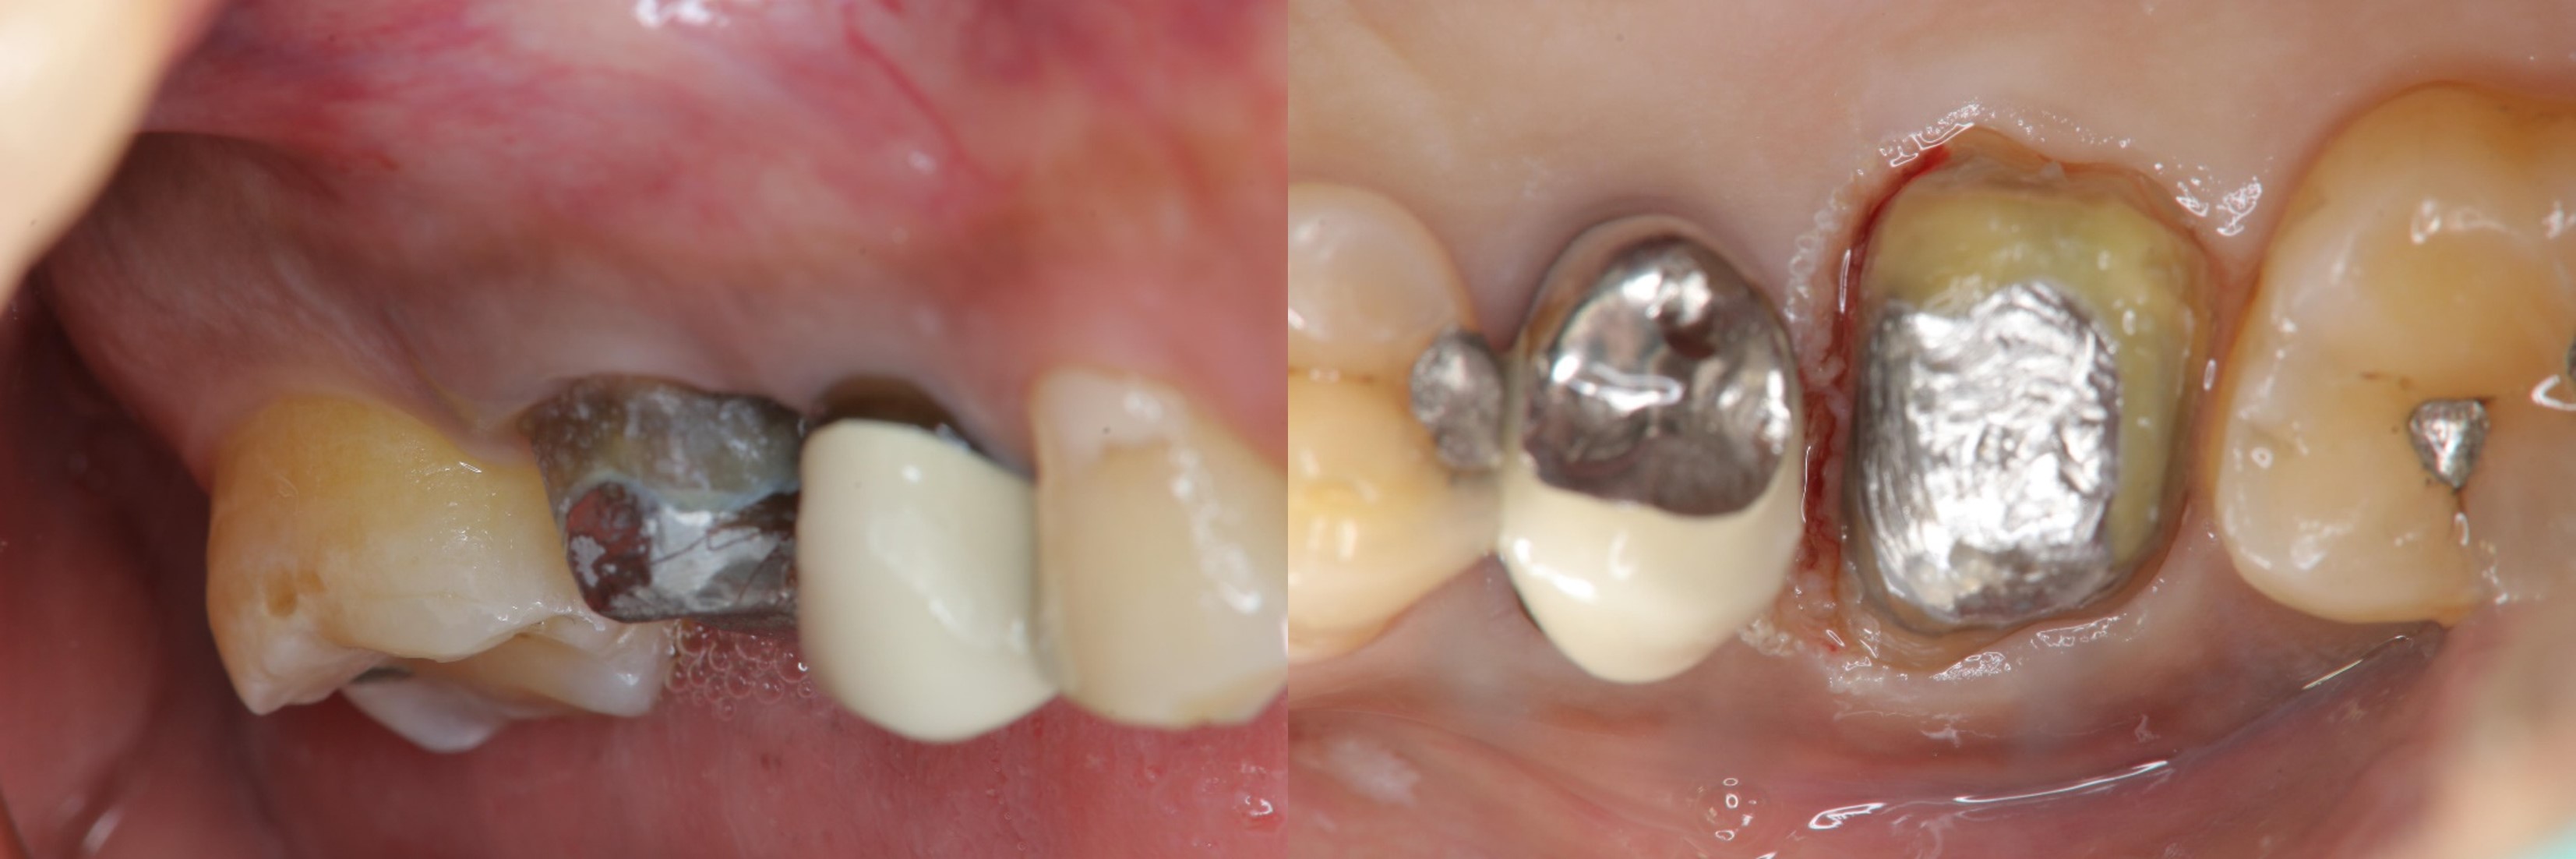

顯微根管重治療

鑄造金屬釘柱

膺復前評估牙齦、牙齒狀態